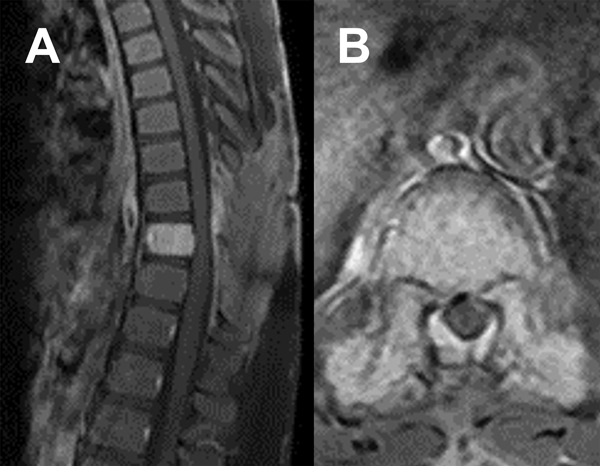

Durante el procedimiento se realizó laminectomía D8 y D9 con exéresis del componente epidural. Durante la cirugía, la lesión fue muy hemorrágica, lo que dificultó la hemostasia. La evolución inicial fue favorable con recuperación progresiva del déficit neurológico. En el cuarto día postoperatorio presentó nuevo deterioro motor. La RM (Figura 3) mostró un hematoma compresivo en el lecho quirúrgico. Se indicó nueva cirugía de evacuación. El paciente logró mejoría continua y progresiva de su déficit.

Figura 3. RM postquirúrgica inmediata. A) Secuencia T2 sagital. B) Secuencia T2 axial.